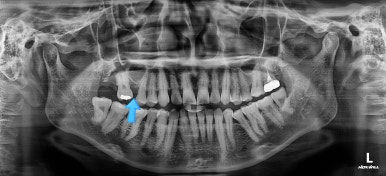

초진 때의 사진입니다.

제일 하단의 X-ray에서 문제점이 보이는데요.

해당 부분의 어금니가 1개가 없었어요.

어금니가 없어진지 꽤 시간이 흘렀기 때문에 몇 가지 문제점이 나타나는데요.